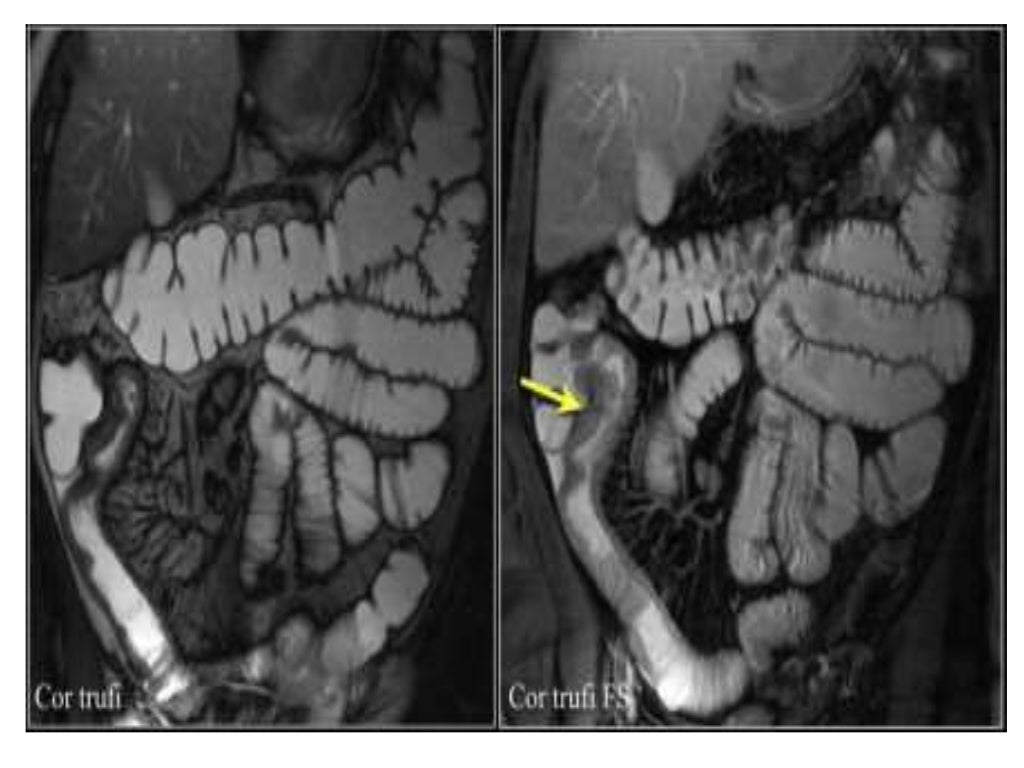

INFLAMMATORY BOWEL DISEASE IMAGING(RADIOLOGY)

INFLAMMATORY BOWEL DISEASE IMAGING(RADIOLOGY) Lab Tests For Inflammatory Bowel Disease Ibd has no cure, but several treatments are available to induce and maintain remission. Laboratory tests are an important component of. Iga and igg antibody testing for s cerevisiae is useful adjunct testing for differentiating crohn's disease and ulcerative colitis. Laboratory tests examine samples of your blood, body fluid, or tissues in order to get information about your. Ibdx® is. Lab Tests For Inflammatory Bowel Disease.